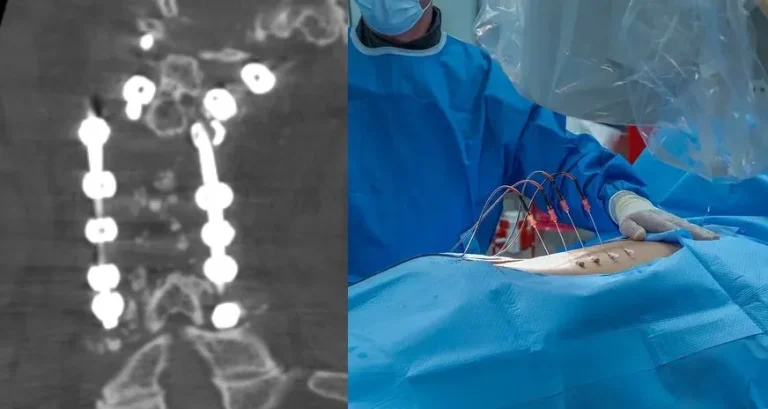

Spinal surgery image with X-ray of metal implants and a surgeon operating on a patient.

ALIF: Highest Complication Rate